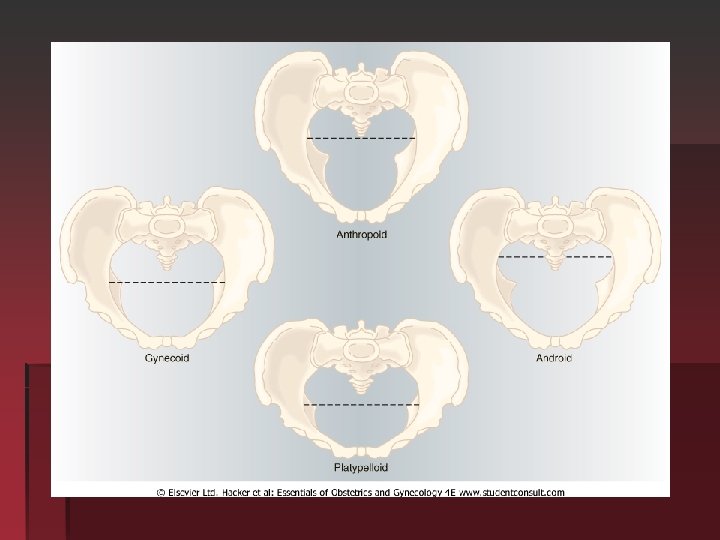

Avariety of pelvic shapes has been described and these may contributed to difficulties in labor

Gynaecoid pelvis Present in 40%of women pelvic inlet is rounded with transverse diameter larger than anteroposterior diameter side wall is straight , well rounded sacroscaitic notch, well curved sacrum , spacious sub pubic angle =90 degree, average prominence of spine , head forced to occipital anterior position

Anthropoid pelvis 20% of female , long narrow oval inlet , long antero-posterior diameter large posterior inclination of sacrum , spine not prominent but close , narrow subpubic angle , precipitate occipitalposterior position and delivery in such

Android pelvis In 30% of women tringular inlet with flat post segment widest diameter closed to sacrum , side is convergent , long and narrow sacrosciatic notch, shallow sacral curve , narrow subpubic arch , prominent spine , forced to be occipittrasverse position (funnel shape) deep trasverse arrest

Platypelloid pelvis Flattened gynaecoid pelvis 3%of female pelvis oval shape inlet , straight or divergent side wall, round sacrosciatic notch , posterior inclination of sacrum , wide bispinous diameter , wide subpubic angle , fetal head engage in transverse diameter increased risk of obstructed labour.